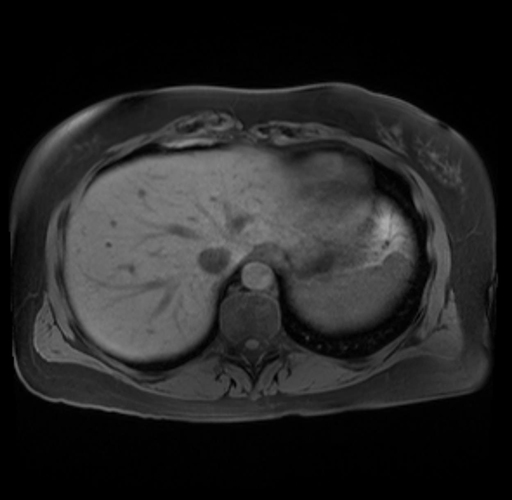

Imaging Analysis

Look through the patient's CT scan to identify any areas of concern for the necessary procedure.

Based on your CT findings, which issue(s) are present and would give reason for "planned slowing down moment(s)" in this case?